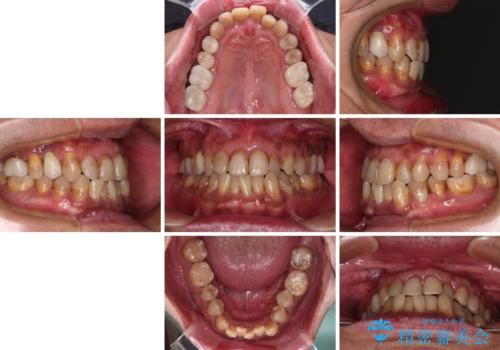

- 前歯のクロスバイトを気にして来院された患者様です。

40代男性で、インプラント補綴治療も経験されている方で、矯正治療をしても良いのかと悩んでいらっしゃいました。

下顎骨の左右のずれがあり、下顎全体が前方に出ている状態であったので、無理をせずにワイヤー装置にて矯正治療を行うこととしました。

クロスバイト改善には難儀しましたが、咬みやすく、笑ったときに清潔感ある口元に仕上げることができました。